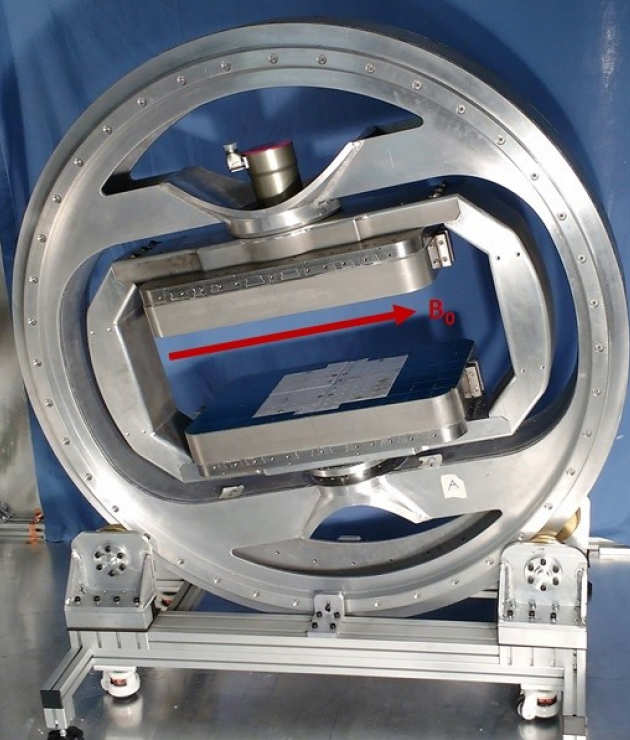

Transverse MRI for Magic Angle Directional Imaging (MADI)

We are creating a moveable assembly with 2 DOF that provides a 'roll' and 'yaw' motion. We aim to utilise this prototype scanner with moving B0 for Magic Angle Directional Imaging (MADI) in vivo.

We are creating a moveable assembly with 2 DOF that provides a 'roll' and 'yaw' motion. We aim to utilise this prototype scanner with moving B0 for Magic Angle Directional Imaging (MADI) in vivo.

Contact:

Karyn Chappell (k.chappell@imperial.ac.uk)

More information is available under the Mechanical Engineering webpage 'Magnetic resonance imaging'.